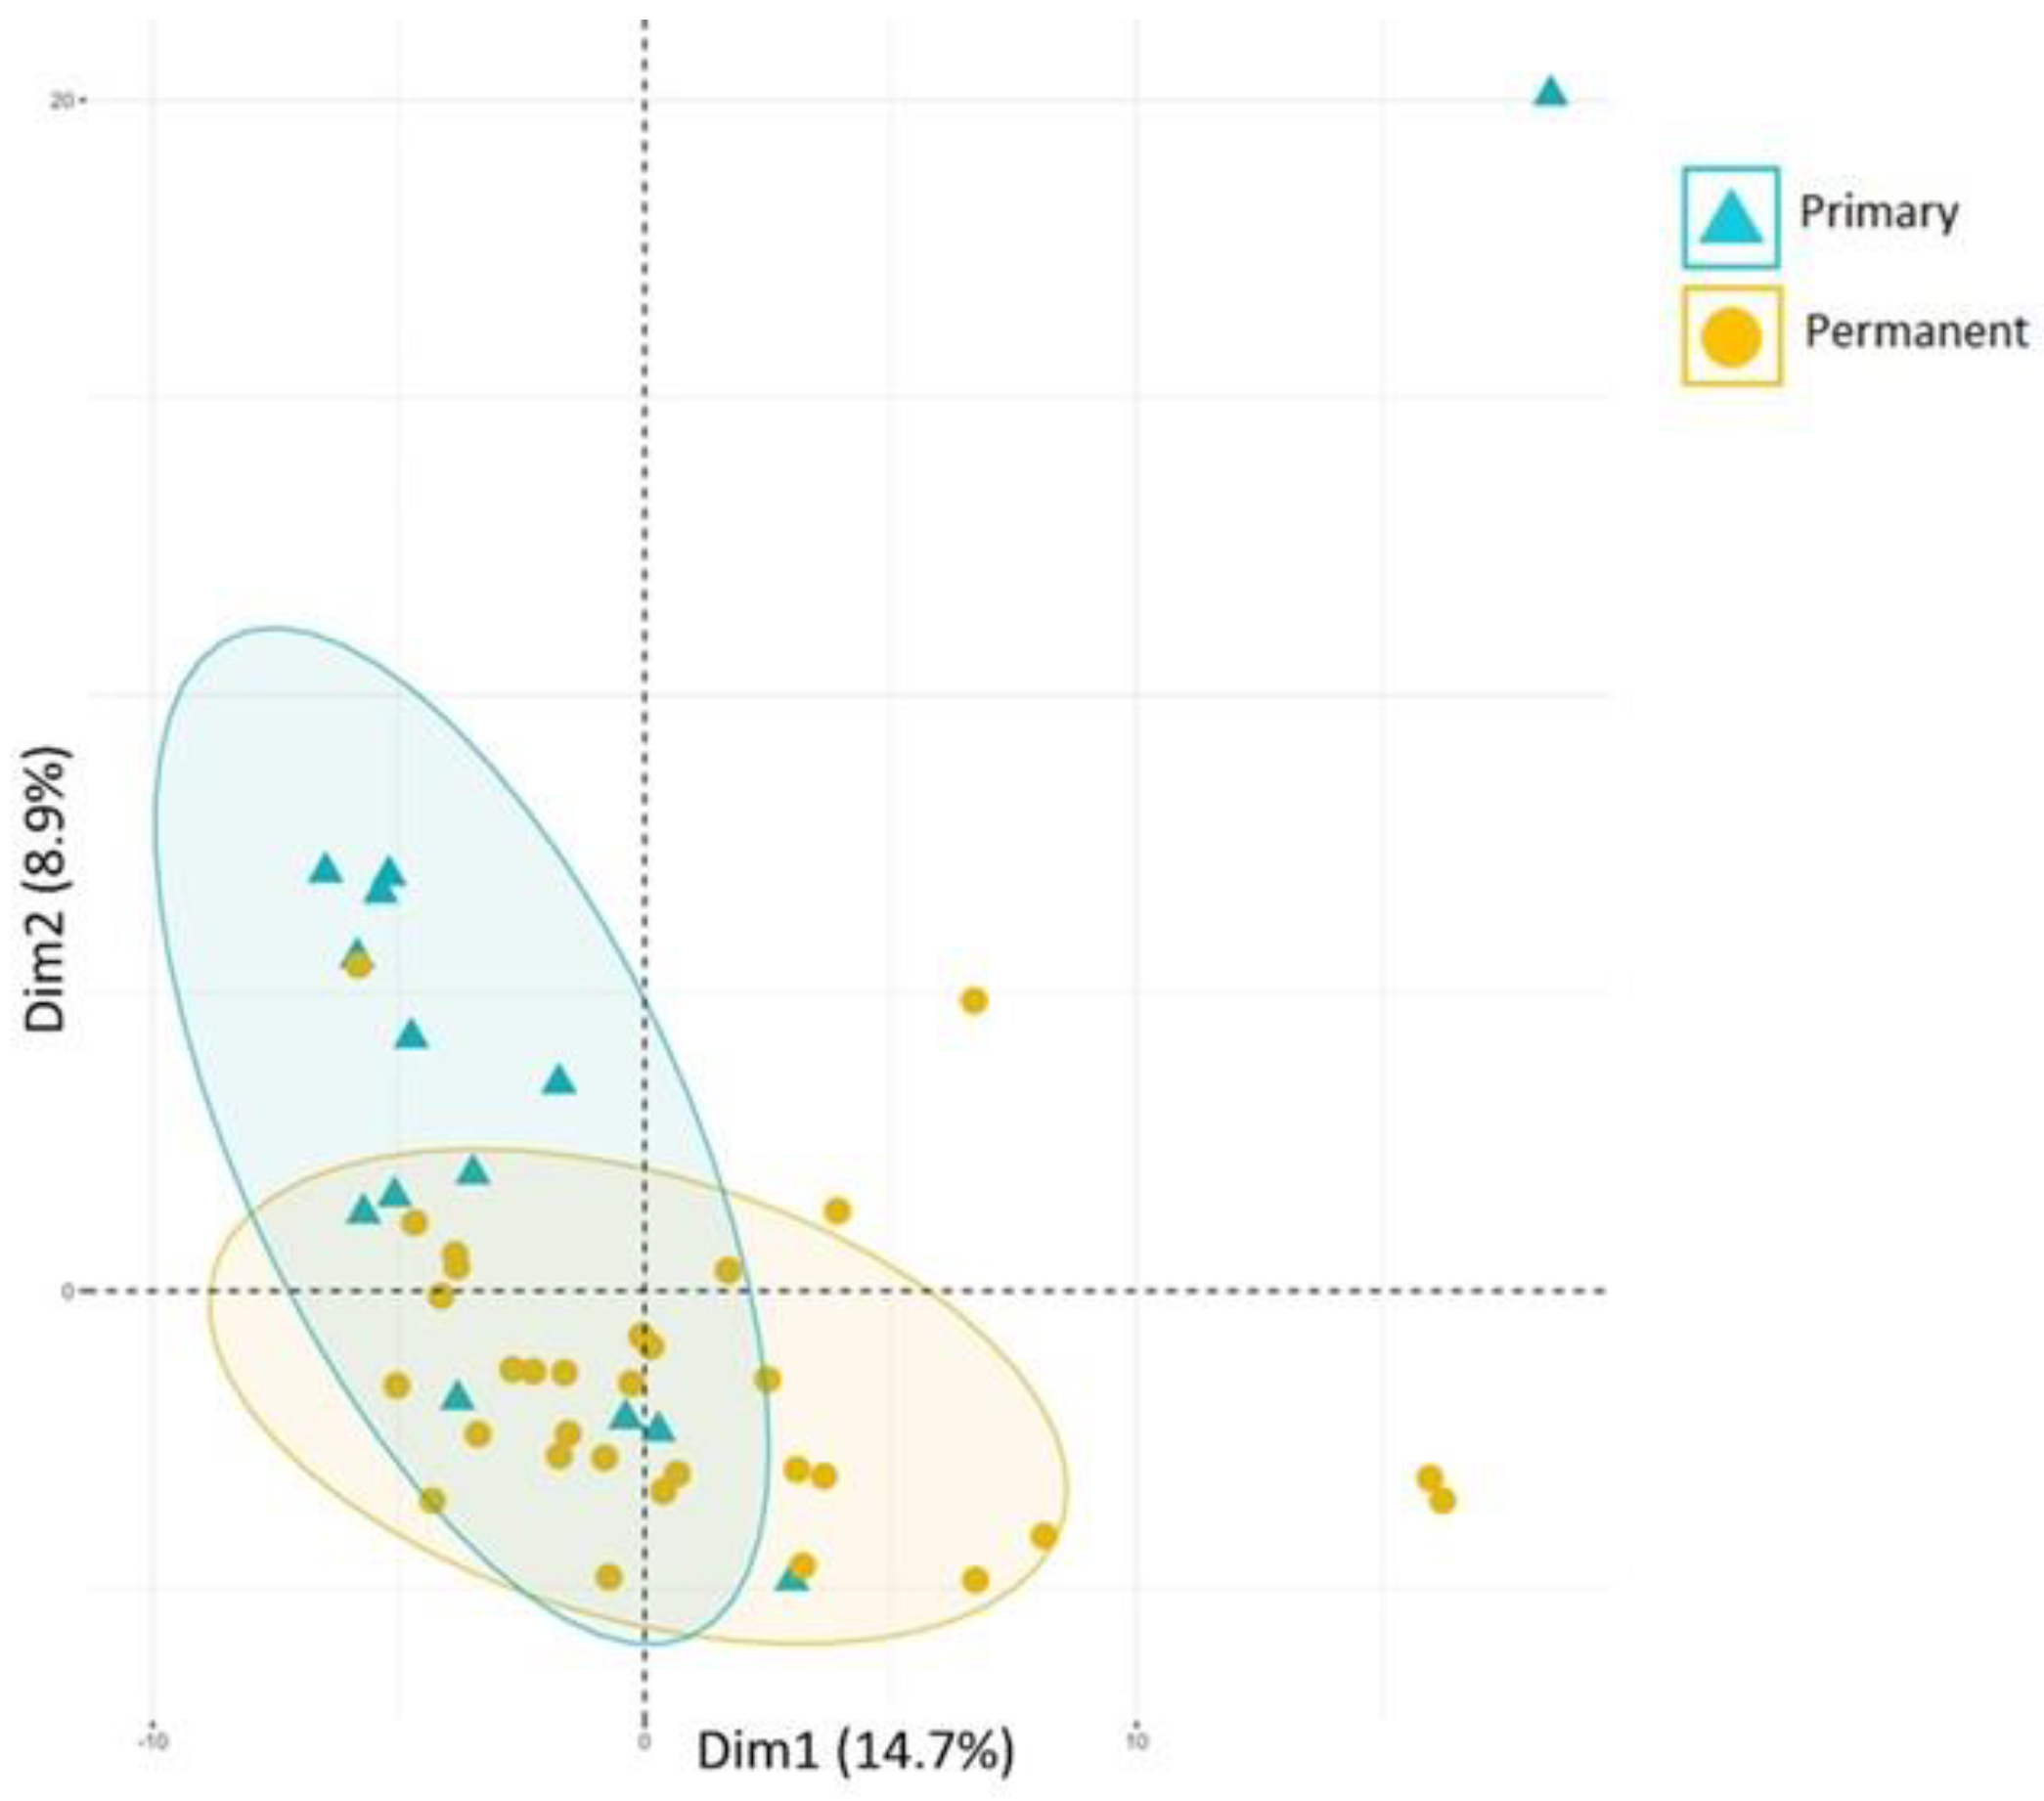

2. Immunological Aspects

- Koo, S.S.; Fernandes, J.G.; Li, L.; Huang, H.; Aukhil, I.; Harrison, P.; Diaz, P.I.; Shaddox, L.M. Evaluation of Microbiome in Primary and Permanent Dentition in Grade C Periodontitis in Young Individuals. J. Periodontol. 2024; Epub ahead of print. [Google Scholar] [CrossRef]

- Shaddox, L.; Hu, J.; Vovk, A.; Huang, H.; Wallet, S.; Harrison, P.; Aukhil, I.L. Hyper-Inflammatory Response between Primary and Permanent Dentition with Aggressive Periodontitis. Int. Assoc. Dent. Res.-J. Den. Res. 2012, 91, 941. [Google Scholar]